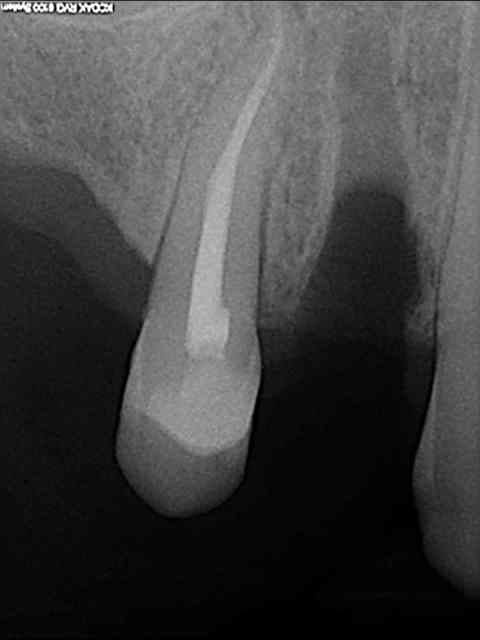

aussitôt demandé, aussitôt fait !!

(j+1 an)

R18 naqzzj - Eugenol

tu as perdu pas mal d'os!!